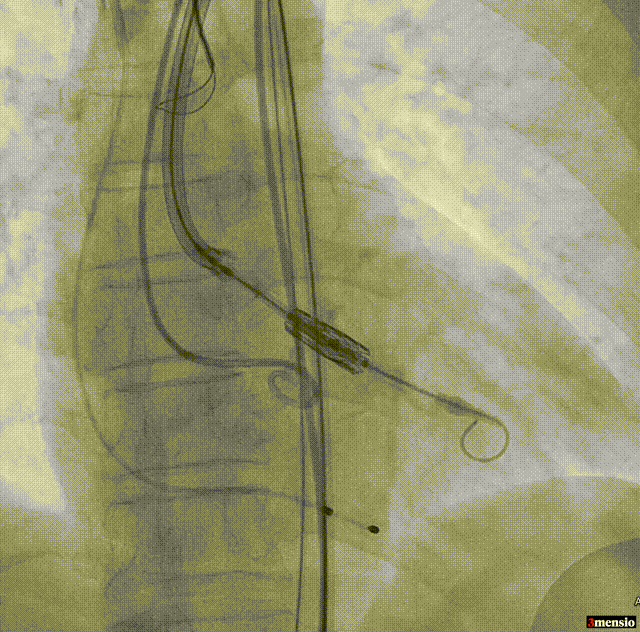

18mm球囊预扩

95/05定位

MuguetA™21 mm瓣膜+1cc释放